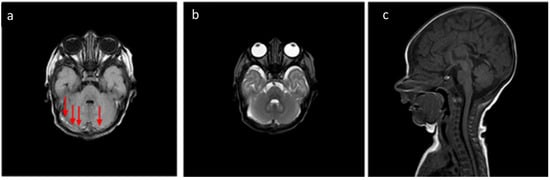

Figure 5. In the same patient in Figure 3, birth-related SDH in an 11-day-old infant born spontaneously:a Axial SE T1-weighted sequence at the level of the basal ganglia—subdural hematoma with occipital and temporal distribution (arrow). (b) FLAIR T2-weighted sequence on the axial plane at the same level as in Figure 4a.The hematoma appears hypointense (arrow) and, considering the hyperintensity on T1, it can be dated as early subacute (intracellular methemoglobin). (c) SE T1-weighted sequence on the axial plane passing through the distal cervical tract confirms (arrowhead) what was described in Figure 4a.

According to SDH locations, the patients were divided into supratentorial, infratentorial, both, and spinal canal (Table 5). Twenty-six patients (83%) showed simultaneous and/or bilateral co-involvement of multiple CNS areas. Cerebellum involvement occurred in almost all patients (31/32, 96.9%) except in one 3-day-old infant. In the cerebellum, bilateral involvement was observed in 78% (18/23) of males and 44.5% (4/9) of females. Parietal and occipital SDH were predominantly bilateral in both genders (68.7% and 100%, males and females, respectively), whereas tentorial hemorrhages were more frequently unilateral. The SDH of the falx cerebri and temporal area were more often bilateral in females, while males exhibited a higher prevalence of unilateral involvement in these areas.